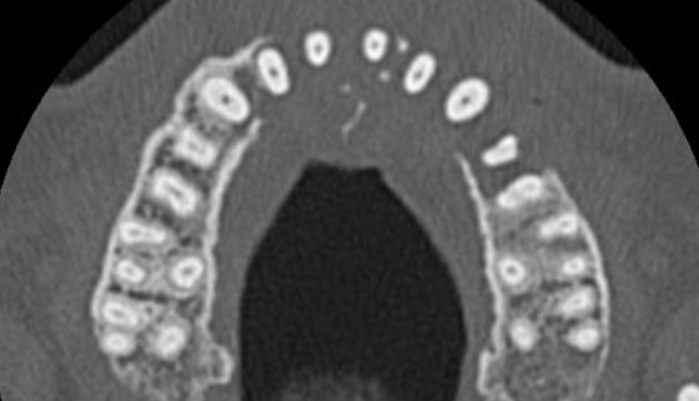

치료비가 저렴한 현지 치과를 찾은 그는 엑스레이 촬영 결과 충격적인 소식을 접했다. 왼쪽 위턱뼈가 보이지 않는다는 진단을 받은 것이다.

정밀 CT 촬영 결과 그의 부비동에서 자라난 종양이 코 아래까지 퍼져 있는 것이 확인됐다.

이미 종양은 그의 위턱뼈를 ‘먹어 치운’ 상태였으며 목까지 전이되기 시작한 상태였다.